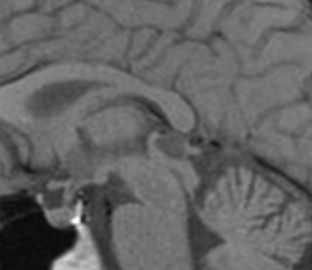

![Ratke cleft cyst]()

МРТ головного мозга. Т1-взвешенная сагиттальная МРТ. Киста кармана Ратке.